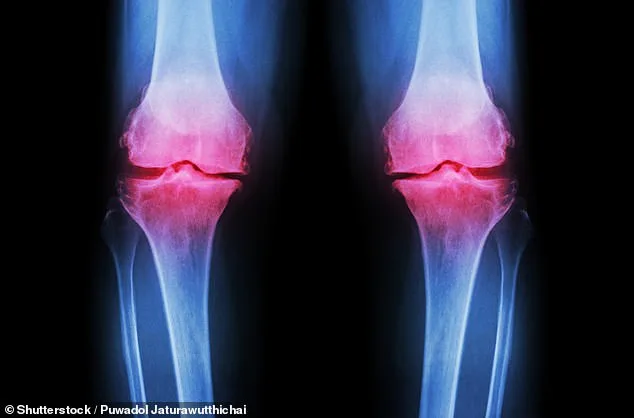

Osteoarthritis occurs when cartilage—the protective tissue between bones—breaks down, causing bones to rub together and joints to swell. Normal joint wear and tear is typically repaired by the body, but excessive strain from repetitive exercise or improper nutrition can overwhelm this process. Post-traumatic osteoarthritis, often linked to fractures in joints like the ankle or knee, is becoming more common among young athletes. 'Improper healing from injuries alters joint mechanics, accelerating cartilage degradation,' explained Sinnett. This condition, which usually appears after 45, is now affecting people as young as 25.